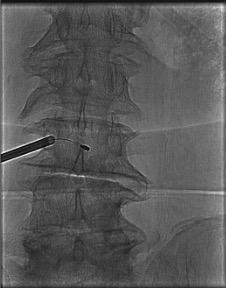

AP View โ "Owl Eye" Pedicle Targeting

- Both pedicles appear as oval or circular targets ("owl eyes") in AP view when the endplate is squared with the fluoroscopy beam

- Advance trocar coaxially within the ipsilateral pedicle oval โ tip should remain inside the pedicle circle throughout advancement

- Trocar medial wall breach (tip crosses the medial pedicle cortex) โ risk of epidural hematoma; stop and recheck

- Final curved cannula tip: at or crossing midline on AP = correct BVF position

- Tip lateral to midline on AP = has not reached BVF; curved cannula entry point too lateral